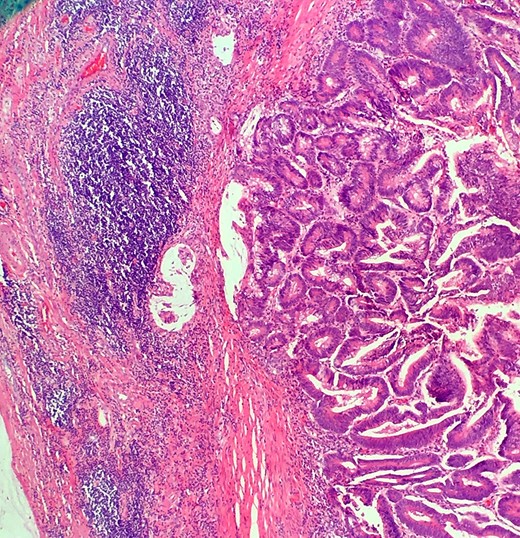

Definitive histological examination showed perforated appendix involved by moderately differentiated mucinous adenocarcinoma (Fig. 5), arising in the background of diffuse tubulovillous adenoma with extensive high-grade dysplasia and showed cellular mucin within the periappendiceal soft tissue (Figs 6 and 7). Proximal cecal mucosal margin and mesenteric margin uninvolved by carcinoma and four periappendicular lymph node was negative for metastatic carcinoma and pathological stage aided for pT4a, pN0. The post-operative course was uneventful. The tumor was staged as T4N0M0 (Modified Astler Coller B3). Patient was referred for oncology and for multidrug adjuvant chemotherapy of 5-fluorouracil, lecovorin and oxalipatin (FOLFOX) was given. Patient was asymptomatic during the 2 weeks, 3 months and 6 months follow up.

This demonstrates mucinous tumor with pushing invasion through the appendiceal wall.